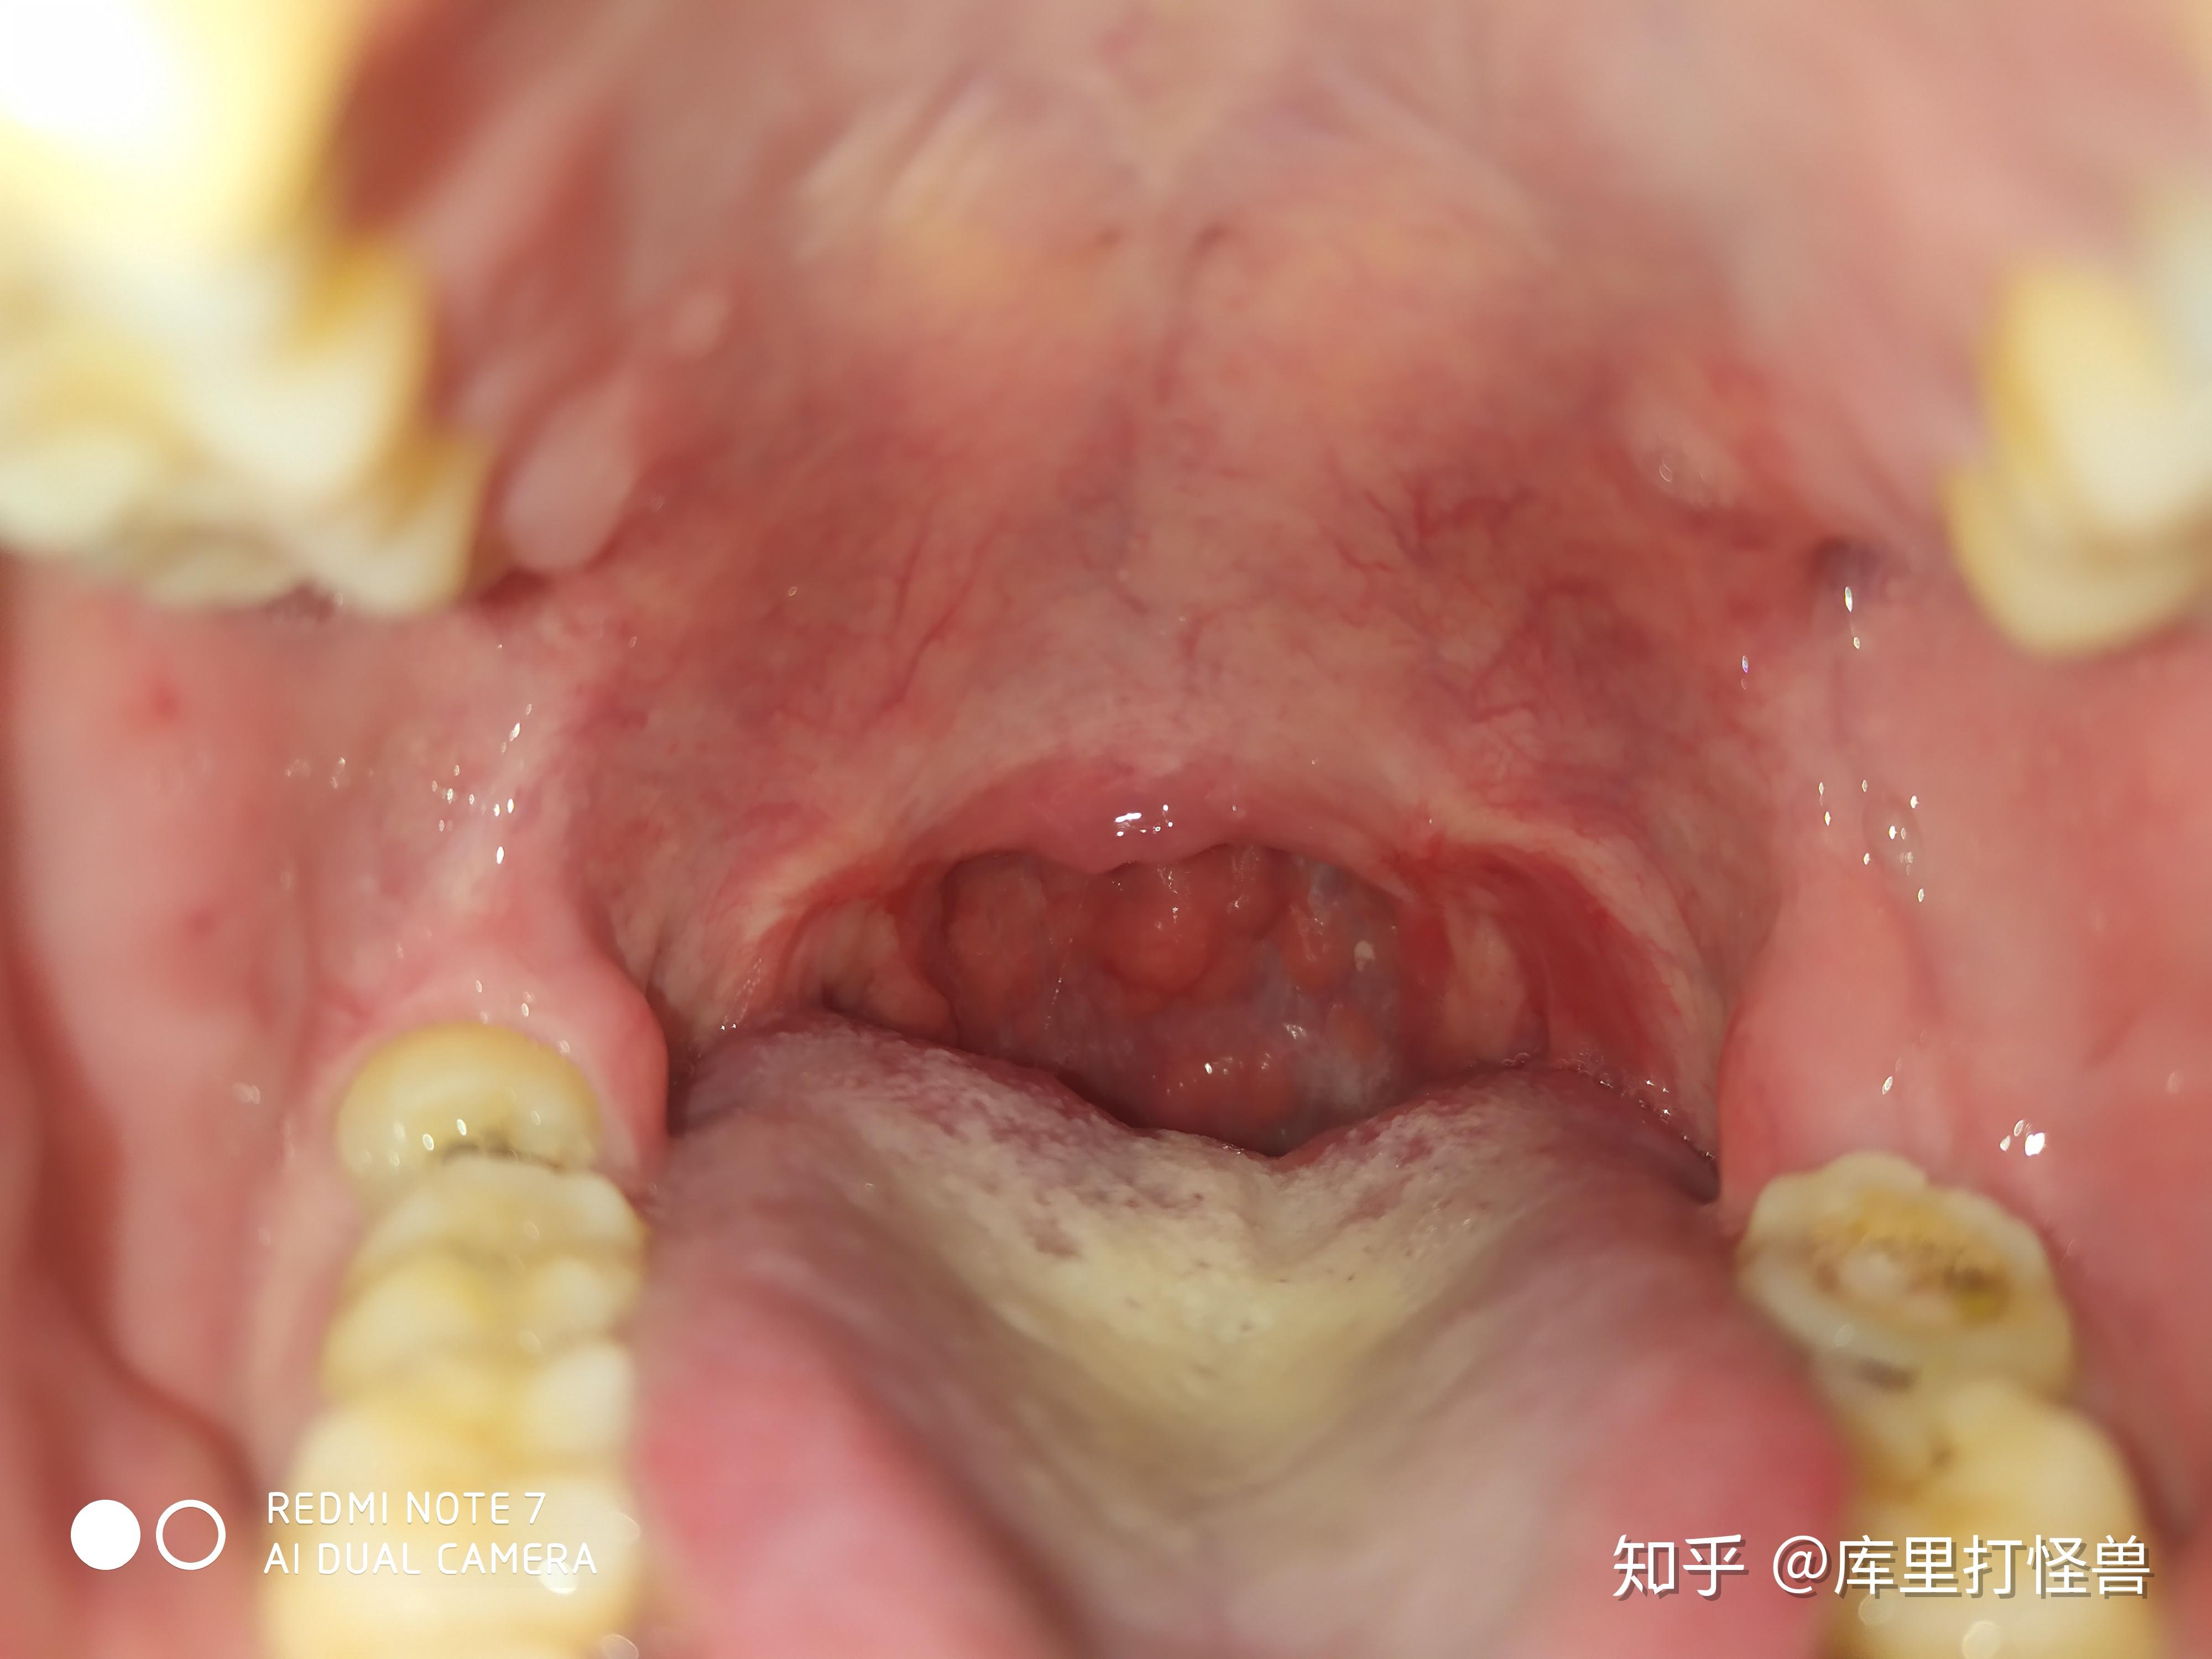

扁桃体切除手术的体验是怎样的? - 知乎

图片尺寸3024x4032